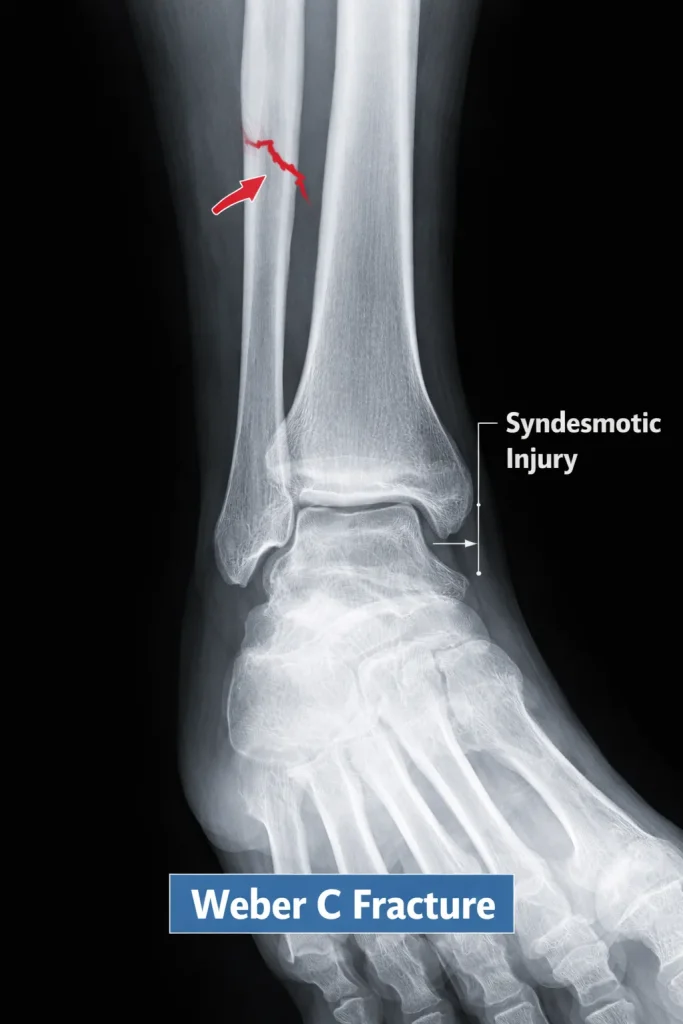

Weber C Fracture

A Weber C fracture occurs above the syndesmosis. These fractures are usually unstable and associated with ligament disruption.

Radiology Features

- High fibular fracture

- Widened ankle mortise

- Syndesmotic separation

Because the syndesmosis is disrupted, surgical stabilization is commonly required.

The goal of surgery is to restore the normal relationship between the tibia, fibula, and talus – known as the ankle mortise. When the mortise is not properly restored, long-term outcomes deteriorate significantly.

Is a Weber C Fracture Serious?

Yes. Weber C fractures are the most serious of the three types. They involve ligament disruption above the syndesmosis, which means the ankle joint loses its structural integrity. Without proper treatment, patients risk:

- Chronic ankle instability

- Progressive deformity

- Early post-traumatic arthritis

- Significant loss of function

Early surgical intervention and proper rehabilitation are critical to achieving a good outcome.